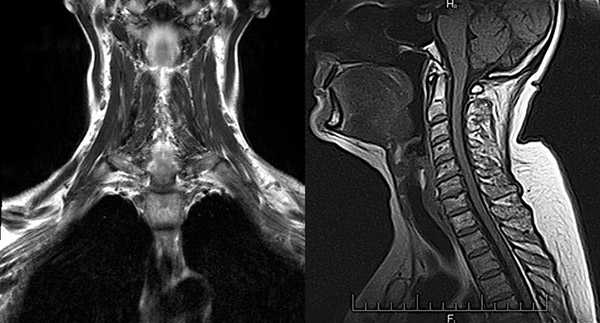

Для выявления болезней слюнных желез (сиалоаденит, синдром Шегрена, закупорка протоков камнями) применяются лучевые методы - КТ, МРТ, УЗИ. Специфичность компьютерной томографии при нозологических формах около 100%, достоверность - 98%. Показатели высокие для достоверной верификации патологии околоушных, подчелюстных желез. Ограничивает повсеместное применение метода радиационное облучение. Разовая обследование не приносит вреда, но не рекомендуется делать сканирование часто (за исключением верификации новообразований).

МР-томография хорошо дифференцирует изменения железистых структур. Стоимость оборудования и техническое обслуживание высокое. Установлены аппараты в крупных мегалополисах, что снижает доступность исследования для населения.

КТ-сиалография применяется при остром и хроническом течении слюннокаменной болезни, сиалоаденита, паротита, паротите Шегрена. Способ позволяет правильно поставить диагноз, выявить локализацию, распространенность, стадию патологического процесса.

КТ-проявления болезни Шегрена

Аутоиммунное поражение железистой ткани сопровождается симметричным изменением органов (с обеих сторон). Использование КТ-сиалографии позволяет выявить специфические проявления нозологии:

- Зернистость поднижнечелюстной и околоушной железистой ткани;

- Снижение плотности;

- Шейная лимфаденопатия;

- Псевдолимфомы;

- Уменьшение размеров слюнных желез.

К аутоиммунному поражению может присоединяться бактериальная или грибковая инфекция околоушно-жевательной области. Томограммы показывают аналогичные нарушения жевательной мышцы, крыловидного пространства, поднижнечелюстной полости.